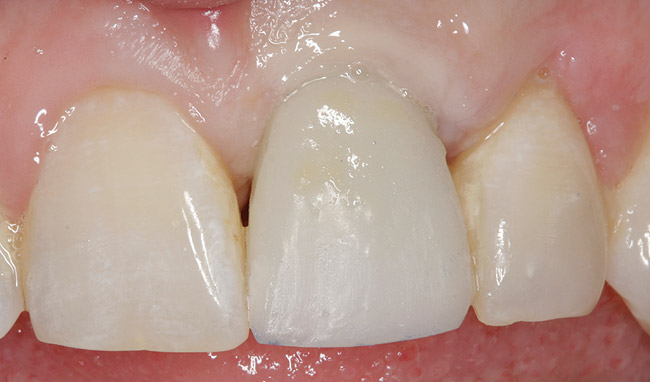

Fig 6. Provisional fabricated, maintaining ideal preoperative soft-tissue position.

Figure 6

A temporary abutment can be placed onto the implant analog and adjusted until the matrix can be seated directly over it. A long coping screw is placed in the temporary abutment, and the vacuum form is perforated to allow for the screw to exit (Figure 5). The vacuum form is loaded with the provisional material of choice and re-placed onto the cast. Once polymerized, the provisional is unscrewed, refreshed, relined, and re-placed onto the model with the soft-tissue outline in bite registration material. The perfect replication of the preoperative tooth emergence contours will now exist (Figure 6).